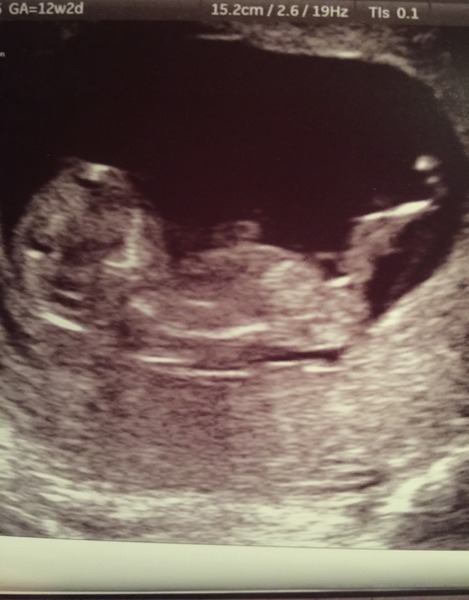

speaking of scans, here's the wee one we got to see yesterday! my due date got revised, too, jw, to 30th july, but i'm definitely going to stay put here now too, if that's ok. it's the most bizarre thing - i'm due on the exact same date as my sister now! what are the odds? we're half a world apart and had no idea the other was trying!

August 2016 (3) - scans fast approaching, teeny tiny bumps appearing, and sickness easing....we hope!